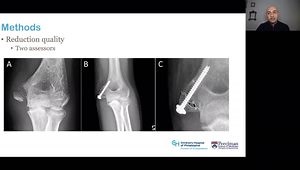

Elbow Dislocation

Pediatric Elbow Pinning: Making it Look Easy! Displaced Supracondy

Open Reduction of Medial Epicondyle Fractures in the Pediat

Planning Ulnar Osteotomy for Posterior Radial Head Dislocation